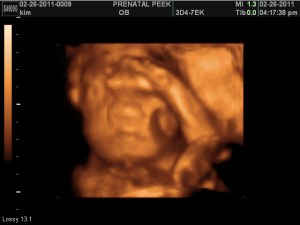

3D Sonogram!!